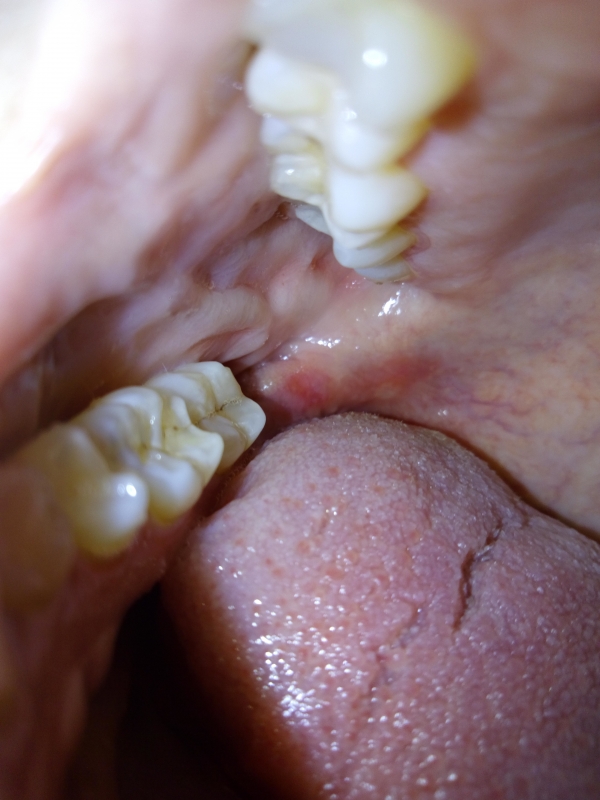

При пальпации на челюсть снизу болезненно. Мягкое небо и десна красные, в месте введения анестезии белые волдыри. Температуры нет, при смыкании зубов болезненные ощущения на зубах, сверху и снизу, стоящих рядом с удаленной восьмеркой. Делаю ванночки с "Хлоргексидином", не помогает.

Удаление зуба мудрости - операция сложная и достаточно травматичная. Болевые ощущения после удаления могут сохраняться около 1 недели. В таких случаях часто назначаются нестероидные противовоспалительные лекарственные препараты (Нимесил). Есть изменения на слизистой оболочке, лучше продолжать делать ванночки с "Хлоргексидином", возможно ещё применение мази "Холисал". Но лучше проконсультироваться со стоматологом-хирургом, который удалял зуб.